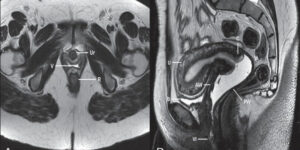

Магнитно-резонансная томография матки и яичников: показания

До недавнего времени диагностика женских болезней была для пациентки неприятным набором медицинских манипуляций. Традиционное гинекологическое обследование с использованием зеркал и других медицинских инструментов не гарантировало диагностику патологических процессов, таких как гиперплазия кисты или рак яичников, низкая степень проходимости маточных труб и т. д. Эта картина изменилась с появлением и применением неинвазивного метода диагностики патологии матки …